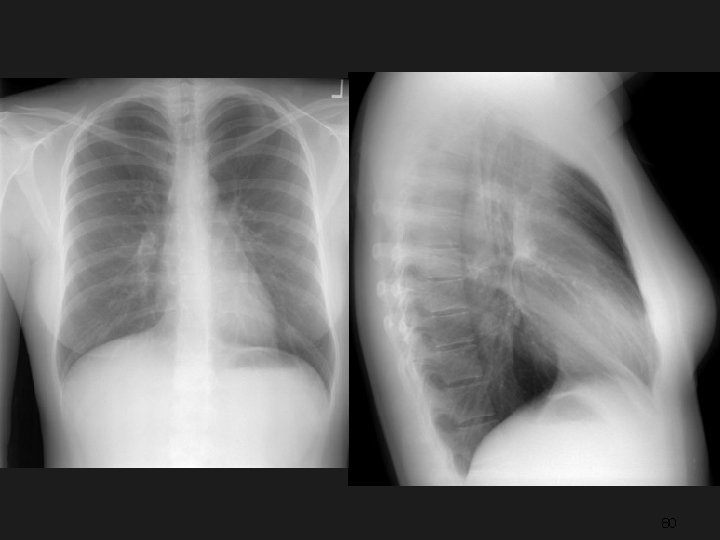

Radiology 1895 Radiology 2001 6